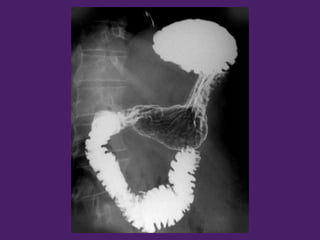

¡¡¡Bonus track 2!!!!!

Tránsito esófagogastroduodenal